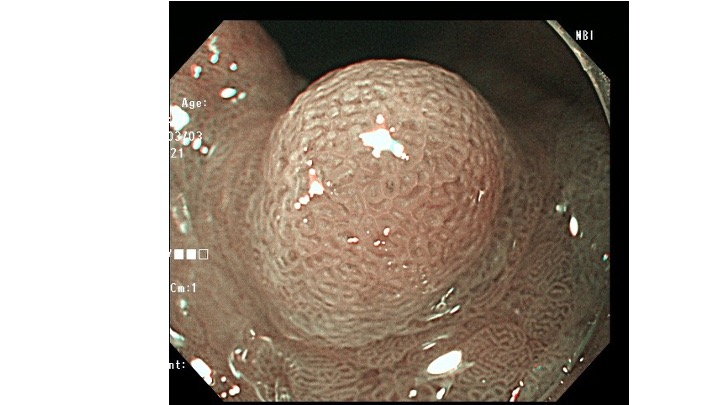

今回提示する症例(ピロリ除菌後)は、隆起型の早期胃癌で、表層に癌の露出を認めない早期胃癌です。

治療日の拡大内視鏡所見です。

通常観察はやや白色調の隆起、NBI観察では、癌の特徴である色差(癌:茶色、周辺:緑色)を認めています。

(1)癌の血管は、視認できず。

(2)表面構造に、癌を示唆する所見も視認できず。